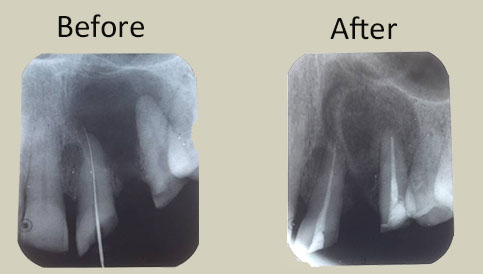

Images of cases done with prp

ENDO-PERIO LESION